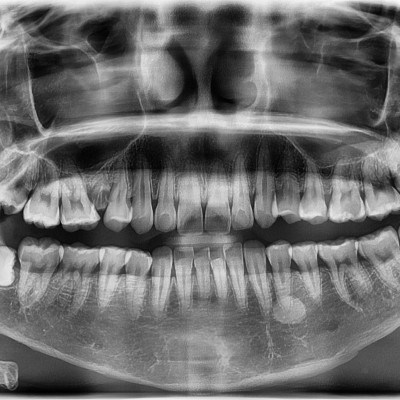

#28,38 사랑니 발치 #28,38 사랑니 발치 구강 외과 전문의가 당일 발치했습니다. --------------------------..

작성자 이턱이 작성일 02-02 조회 3